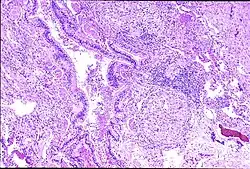

Peribronchal non-necrotizing granuloma from berylliosis | |

Granuloma formation is seen in other diseases such as tuberculosis and sarcoidosis. Sarcoidosis, like berylliosis, also produces granulomas without a necrotic core, and so distinction between the two processes can be difficult.